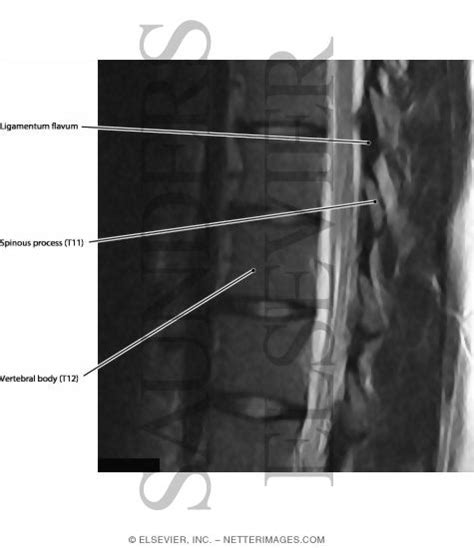

Ligamentum Flavum - Lumbar ossified yellow ligament Alugolu R, Rambarki O ... / Ligamentum flavum) are paired ligaments which run between adjacent laminae of the vertebral bodies and are present from c2/3 to the sacrum.

Assessment of traumatic brain injury assessment. Due to its location in the spine. 2 фразы в 1 тематике. Ligamentum flavum hypertrophy, also known as ligamentum flavum thickening, is a health condition related to the spine and lower back. The ligamentum flavum forms a cover over the dura mater: Each ligamentum flavum connects two adjacent vertebrae, beginning with the junction of the axis and third cervical vertebra. Anatomy of the ligamentum flavum between adjacent laminae. It is an extremely elastic ligament, which connects the spinal bones through its two laminae, articular joints.

Anatomy of the ligamentum flavum between adjacent laminae. The elastin pulls the ligament out of the. The ligamenta flava (singular, ligamentum flavum, latin for yellow ligament) are a series of ligaments that connect the ventral parts of the laminae of adjacent vertebrae. Meaning of ligamentum flavum medical term. The superficial ligamentum flavum inserts onto the superior edge and posterosuperior surface of the caudal lamina. Jaune (ligamentum flavum), dont peu d'études sont rapportées dans la littérature, a plusieurs particularités mises en évidence dans ce. Проверьте 'ligamentum flavum' перевод на английский. Ligamentum flavum is perhaps the most clinically significant soft tissue in the spine.